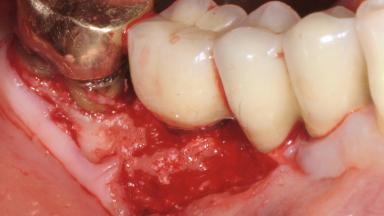

Reconstructive Treatment of a Peri-Implantitis Defect at an Implant in a Mandibular Molar Site

In this case, Mario Roccuzzo utilizes surgical bone regeneration treatment around implant 46 using a bone graft substitute and a connective tissue graft to resolve peri-implant inflammation, reduce the probing depths, and prevent further progression of disease.

A 58-year-old-male patient was referred in February 2007 for implant placement in the right mandibular molar area. Two tissue level implants were inserted at sites 44 and 46, respectively, to support a three-unit fixed dental prosthesis (FDP).